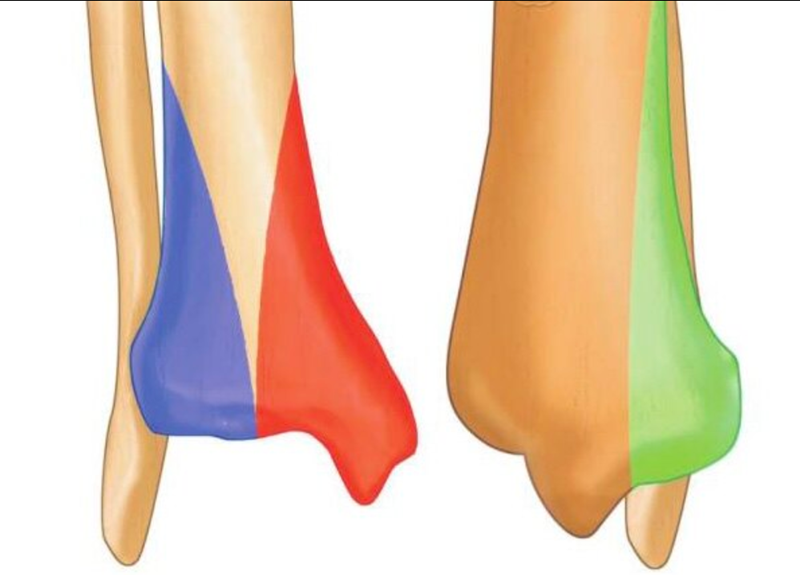

图2 胫骨远端解剖分区,红色内侧柱;蓝色外侧柱;绿色后侧柱